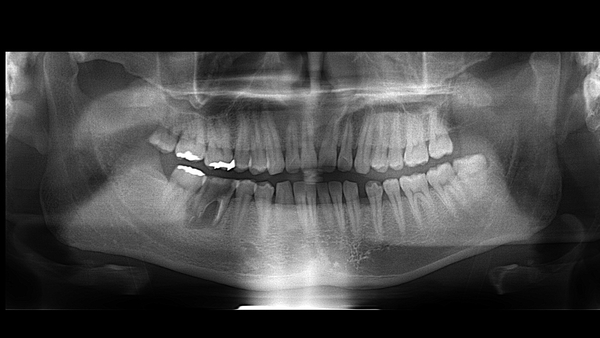

| 患者 | 30代男性 |

| 主訴 | 「歯が腫れてなかなか痛みが引かない、物が噛めない」という状態でした。 歯の揺れ、痛みが引かないので知り合いに紹介されて来院されました。 |

| 診断 | 歯根破折の長期放置による慢性歯根膜炎であり、この状態が長かったため周りの骨が喪失していました。 |

| 治療内容 | 何軒かの歯科医院で抜歯後インプラントを勧められたとのことで、納得しているのでその方法を当院でお願いしたいと言われました。 しかし、この骨の喪失状況は尋常ではなく、抜歯後の硬組織、軟組織の喪失量はかなりのものと考えられ、それを補いかつインプラントを埋入する難しさを説明しました。 幸い患者の年齢が若く、適した親知らずが残っていることを説明し、歯牙移植の提案をしました。 患者様にはこの提案を喜んでいただき、受け入れられました。 私が歯牙移植を提案した理由は以下の3つです。 この3に期待したのが一番の理由でした。 |

| 治療期間 | 6ヶ月(経過観察中) |

| 費用 | 100,000円(税抜) |

| 治療後の経過 | 現在予後は良好 |

| 治療のリスク | 長期にわたり徐々に歯が外部吸収することがあります。 |